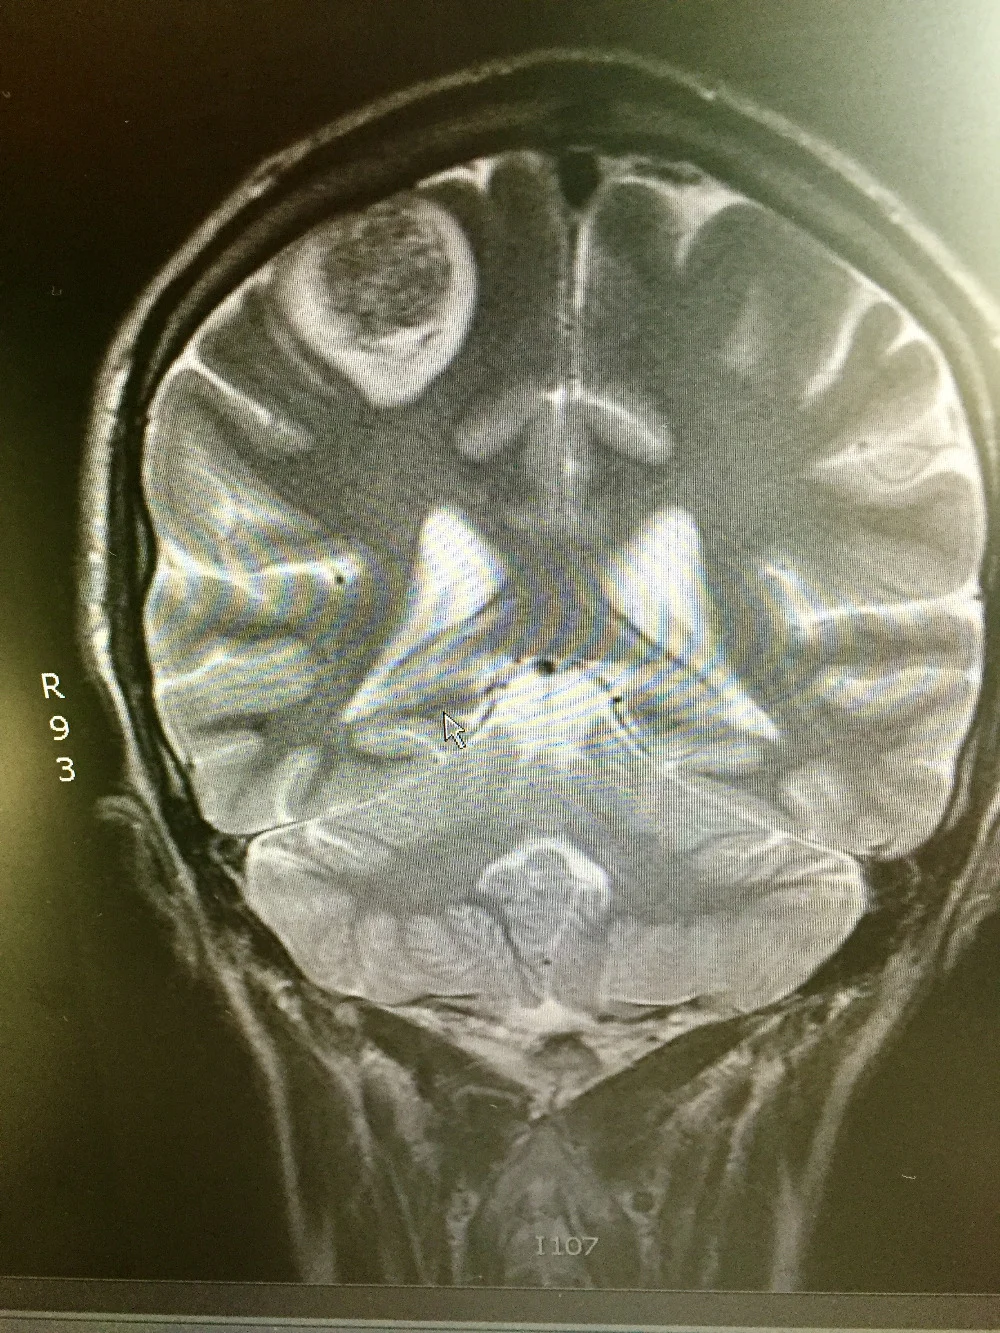

The following day, yesterday morning, while driving back from an appointment, I lost complete mobility in my left arm. unsure if this was a seizure, a stroke... a clotting issue, my sister took me to the ER. as most of my ER stories go, they did a number of tests, the first of which, after vitals, was a CT scan of the head. what they discovered explained the loss of mobility/motor function in my left arm -- a 3.2cm lesion located on the back rear (right) lobe in and around parietal and occipital lobe. (this is what im piecing together from the various doctors I've met. still trying to grasp the facts.) the MRI i had on jan 30 showed no sign of this (what is assumed to be) metastatic spread.

Unlike the other brain lesion that was dealt with using solely stereotactic radiosurgey (SRS) in early October (2016), this one will initially be surgically resection and then SRS will be used. the main reason for that is its size.

rather than just being swelling from the lesion causing pressure, the surgeon feels part of the lesion (part of it) was pushing against one of the primary motor cortex bands that run along this particular section of the brain. i am still trying to wrap my head around this… but it does explain the continued immobility of the extremity.